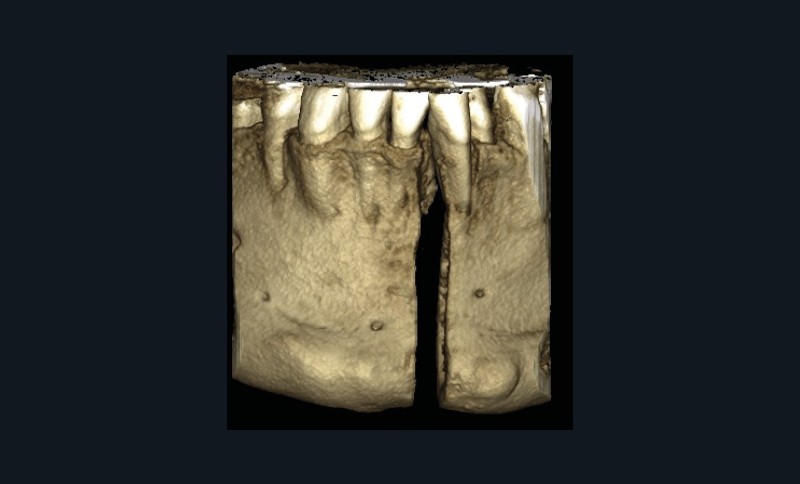

Le Dr Christophe Dunglas développera ensuite l’intérêt du cone beam lors de la mise en place des canines incluses difficiles. En effet, la préparation d’ancrages adéquats et de gestes chirurgicaux a minima préviendra l’apparition de résorptions radiculaires et de lésions parodontales.

À côté de la coopération moindre qu’ils exigent, les ancrages squelettiques présentent également l’avantage de répondre à des indications très variées : correction des sourires gingivaux (Dr Skander Ellouze, fig. 3a-c), distalisation ou mésialisation molaire, supports pour les masques faciaux, mini transpalatin sur vis après expansion, ressorts de rétraction pour mettre en place les canines incluses sans léser les racines des dents adjacentes [3] (Dr Stéphane Renger, fig. 4) ou appareils d’expansion maxillaire (Dr Hans Winsauer, Dr Guido Sampersmans, fig. 5a-c)…